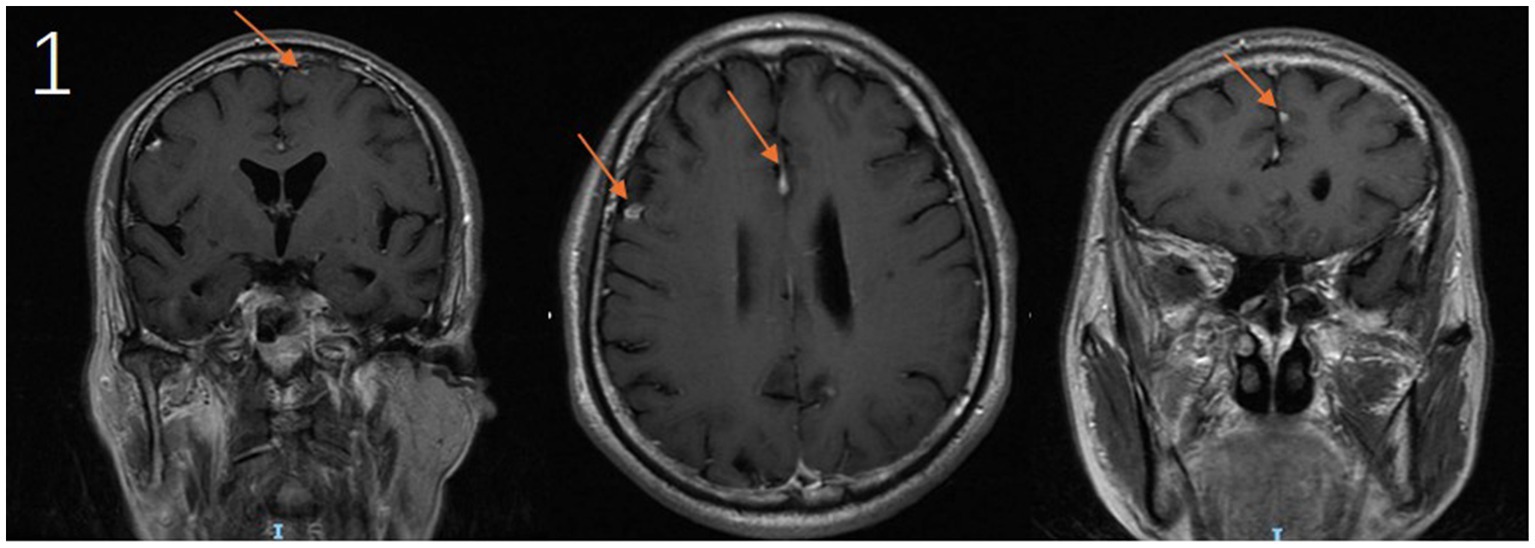

Upon admission, the patient underwent a comprehensive diagnostic evaluation. Chest computed tomography (CT) identified a nodular lesion within the posterior segment of the right upper lobe. Cranial magnetic resonance imaging (MRI) demonstrated multiple contrast-enhancing lesions involving the left frontal lobe, parafalcine region, right frontal lobe, and the sulcus of the left parietal lobe (Figure 1). Laboratory investigations revealed elevations in the erythrocyte sedimentation rate (ESR) and high-sensitivity C-reactive protein (hs-CRP), while the white blood cell count, neutrophil percentage, and procalcitonin (PCT) level remained within normal limits. Cryptococcus neoformans capsular antigen test (CrAg) returned a positive result (Table 1). Additional testing, including autoantibody screening, (1,3)-β-D-glucan assay, Aspergillus galactomannan antigen testing, and HIV antigen/antibody assays, yielded negative results. No microbial growth was observed in cultures of bone marrow, blood, or bronchoalveolar lavage fluid. In light of the suspected malignant pulmonary nodules, the patient subsequently underwent bronchoscopy with biopsy. Histopathological examination of the endobronchial biopsy confirmed squamous cell carcinoma. In response to persistent headache and fever, a lumbar puncture was performed, which revealed an opening CSF pressure of 112 cm H₂O. CSF analysis demonstrated pleocytosis, elevated protein concentration, and hypoglycorrhachia. No malignant cells were identified on cytological examination (Table 2).

Figure 1. Cranial MRI demonstrates contrast-enhancing lesions in the following locations: the left frontal lobe, parafalcine region, right frontal lobe, and adjacent to the sulcus of the left parietal lobe (arrows).